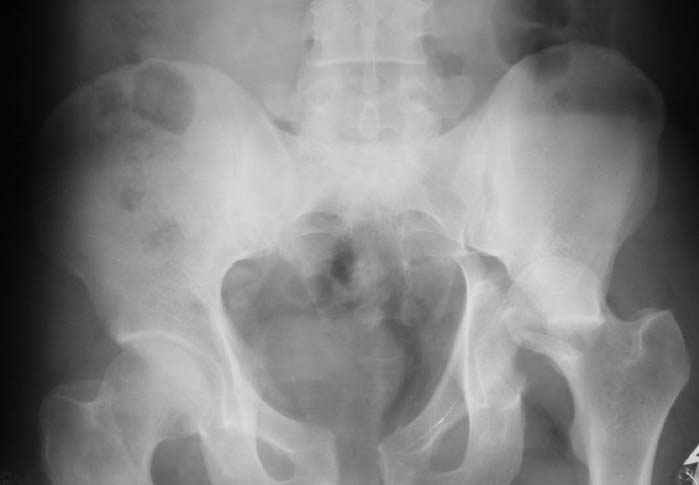

Уважаемый Антон, у Вашего больного имеется транстектальный поперечный перелом вертлужной впадины с переломом заднего края, перелом заднего типа, подвздошный вывих, возможна импрессия и повреждение нерва. Головка при этих повреждениях в нагружаемой части должна быть целой.